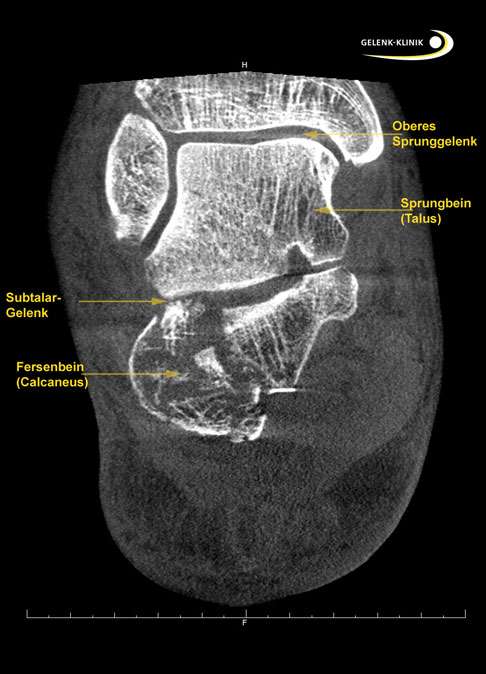

Die bildgebende Untersuchung: Röntgen, Ultraschall und MRT

Subtalare Arthrose im Röntgenbild:

- Schmaler oder aufgehobener Gelenkspalt.

- Osteophyten (Knochensporne) am Rand der Fußgelenke.

- Subchondrale Skelerosierung (Verdichtung) der Knochen unter dem Knorpel).

- Knochenzysten unter dem Gelenkknorpel.

Da die Arthrose einen Verlust des Knorpelüberzugs der Gelenkflächen aufweist, kann mittels bildgebender Verfahren (Röntgen, CT, MRT) eine Verengung des Gelenkspaltes nachgewiesen werden. Wir führen hier stets Röntgenbilder unter Belastung beider Füße durch. Die beidseitige Ansicht im Röntgenbild ist wichtig, um unterschiedliche Entwicklung der beiden Füße und Sprunggelenke im Vergleich zeigen zu können.

Eine MRT-Untersuchung kann zudem die Situation in den Knochen darstellen: Knochennekrosen sind gut sichtbar in der Magnetresonanztomografie. Auch Weichteile und Sehnen (v.a. die für die Funktion des Fußgewölbes wichtige Tibialis Posterior-Sehne) kann im MRT gut dargestellt werden.